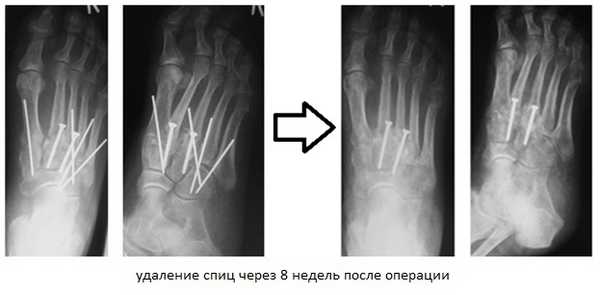

При смещении более 2 мм, нестабильности при функциональных тестах - рекомендовано открытое устранение вывиха с жёсткой фиксацией винтами или пластинами. Используются один или два продольных доступа в 1 и 2 межплюсневых промежутках. После обнажения первого предплюсне-плюсневого сустава первым этапом устраняется межклиновидная нестабильность, вторым этапом устраняется предплюсне-плюсневая нестабильность. В послеоперационном периоде сразу начинается разработка активного объёма движений. Нагрузку на стопу начинают постепенно, с тем чтобы полностью её восстановить к 6-8 неделе. Удаление спиц Киршнера производится через 6-8 недель, компрессирующих винтов через 3-6 месяцев. Возвращение к полной физической активности не ранее 9-12 месяцев после операции.

В ряде случаев целесообразно применить смесь хирургических техник. Если рассматривать весь сустав Лисфранка разбив на внутренний, центральный и наружный отделы, то его внутренний (1) и латеральный (4-5) отделы подвижны, хотя и с малой амплитудой, а центральный (2-3) практически не подвижен. По этой причине в хирургической практике часто используется неполный артродез, то есть выполняют артродез 2-3 предплюсне-плюсневых суставов а 1,4,5 временно фиксируют спицами.

Это позволяет сохранить нормальную биомеханику стопы и предотвратить раннее развитие артроза в смежных суставах которое характерно для полного артродеза.

После осмотра в отделении ортопедии №2 ГКБ №13 принято решение о проведении операции - открытому устранению вывиха, артродезе 1-2-3 плюсне-клиновидных суставов, 1 межклиновидного сустава при помощи винтов и пластины, трансартикулярной фиксации спицами 4-5 плюсне-клиновидных суставов.